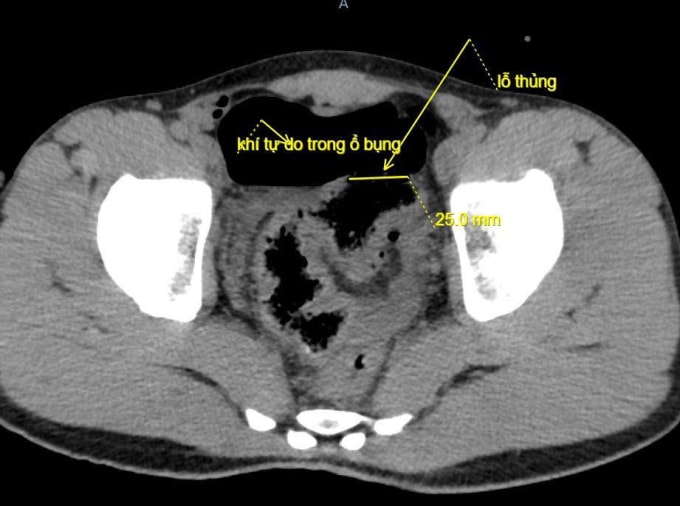

Ngày 20/10, đại diện Bệnh viện Đa khoa Lạng Sơn cho biết bệnh nhân đau bụng dữ dội, bụng chướng căng, khó thở và mệt lả. Kết quả chụp X-quang và CT thấy nhiều khí tự do trong ổ bụng bệnh nhân, bác sĩ nghi ngờ thủng tạng rỗng, chỉ định mổ cấp cứu.

Quá trình mổ, các bác sĩ ghi nhận khoảng 100 ml máu và dịch bẩn trong bụng bệnh nhân, đại tràng sigma có đoạn tổn thương dài 5 cm, thủng khoảng 2 cm và xung quanh dập nát. Bệnh nhân được cắt lọc lỗ thủng, khâu đoạn đại tràng tổn thương, làm sạch ổ bụng và đặt dẫn lưu.